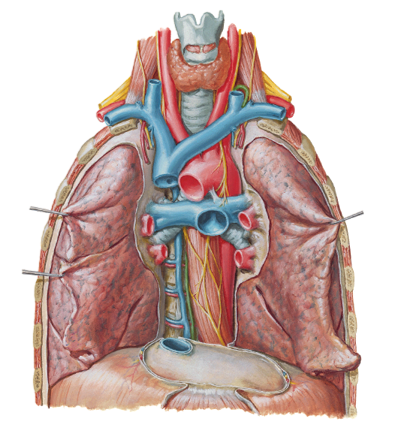

pulmonary circulation: how many pulmonary veins are there?

show the pulmonary trunk, 2 pulmonary arteries and 4 pulmonary veins in the picture?

4....2 on the right and 2 on the left

big blue tube in middle is the pulmonary trunk...two blue pathways going in either direction from this are your right and left pulmonary arteries...then you can see the 4 little red vessels coming in from the sides going back to the heart (pulmonary veins)

briefly summarize the pulmonary circulation

- Deoxygenated blood from your body enters the right atrium of your heart through the superior vena cava and the inferior vena cava.

- From the right atrium, the deoxygenated blood drains into the right ventricle

- The right ventricle then contracts, forcing the deoxygenated blood through the pulmonary semilunar valve up top and into the pulmonary artery

- The pulmonary artery carries the blood that’s very low in oxygen to the lungs, where it becomes oxygenated.

- Freshly oxygenated blood returns from the lungs to the left atrium of the heart via the pulmonary veins...then goes into left ventricle to them get pumped to the peripheries

notice the hilum of the lungs and the pulmonary trunk and the superior and inferior vena cava and the aortic arch